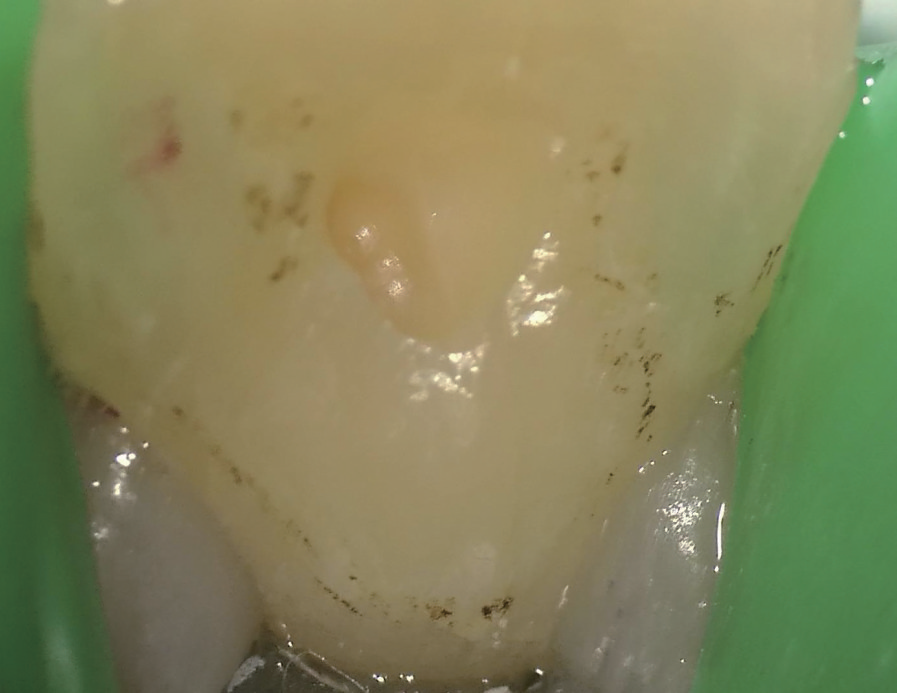

治疗过程   显微镜下可见11牙冠唇侧(图4)和腭侧(图5)存在数个大小深浅不一的裂纹,开髓至牙本质层(图6),患者表示无任何不适,开髓后就闻到髓腔内有臭味溢出,但患者依然无疼痛,经确认11牙髓已坏死(图7)。随后进行根管预备、次氯酸钠溶液冲洗、纸尖干燥(图8)、试主尖(图9),因根尖呈开口状,决定将牙胶尖四周覆盖MTA进行根尖封闭(图10~12),X线片显示根充密合,后续封闭根管中部和冠部(图13),并用光固化复合树脂充填11牙冠(图14),调磨抛光,再次拍摄根尖X线片确认治疗结果(图15),嘱患者定期复查,观察患牙。

图6 未给予局部麻醉下,施行11 开髓,深达牙本质层,患者无任何不适

牙胶尖什么颜色MTA的临床应用——陈志平教授_https://www.jmylbn.com_新闻资讯_第7张

图7 11 髓腔一经打开即有臭味溢出,显微镜检查后确认11牙髓组织已坏死